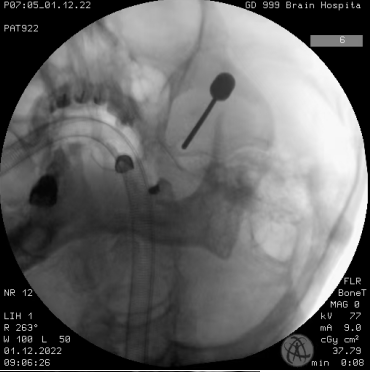

我院神经外一科主任张良接诊了患者。根据影像检查资料,可见小脑上动脉骑跨走行在左侧三叉神经颅内段,患者的左侧三叉神经存在血管压迫造成的“漏电”问题,诊断患者为原发性三叉神经痛。张良告知患者,“三叉神经痛可是‘天下第一痛’,需要手术治疗。”一听到要手术,李大叔就慌了,非常排斥开颅手术。根据患者的情况,张良建议他可以考虑微球囊压迫术,这是一种微创的治疗方式,无需开颅。

完善相关检查,张良团队为患者实施经皮穿刺左侧三叉神经经半月节微球囊压迫术。术后第二天,李大叔惊奇地发现左侧面部疼痛消失,很快就顺利出院了。